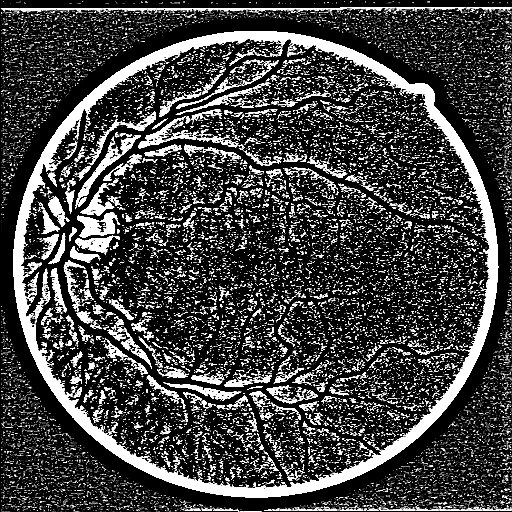

Refer to caption

(a) Input

(b) GT

(c) M-Net

(d) AG-Net

(e) BL

(f) BLST

(g) Ours

Figure 4: Example results for DRIVE. M-Net, AG-Net, and BL disregard some edge structures, which are very similar to textures. Conversely, by decomposing structures and textures, BLST gains better discrimination power and detects more tiny structures. Comparing (f) and (g), when adding the texture block, more tiny boundary structures are detected.

We remove the texture block, structure loss ssubscript𝑠{\mathcal{L}}_{s}, and texture loss tsubscript𝑡{\mathcal{L}}_{t} from STD-Net and name the baseline model as BL. The model BLST is formed by adding the structure-texture loss into BL. Fig. 4 shows a test example, including the ground truth vessel (GT) and segmentation results obtained by M-Net, AG-Net, BL, BLST, and the proposed STD-Net. The experimental results of BL and BLST are shown in Table 3.